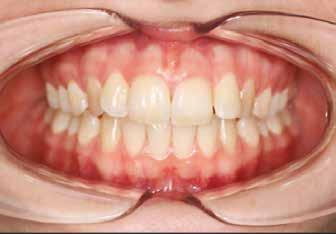

A 19 éves hölgypáciens azzal a kéréssel jelentkezett a rendelőnkbe, hogy szebb fogakat szeretne. Az első konzultáció alkalmával megkérdeztük, hogy mi zavarja leginkább a fogazatának jelenlegi megjelenésében, valamint azt is megbeszéltük vele, hogy milyen végeredmény elérése esetén lenne maradéktalanul elégedett. Ebben az esetben a kezelési célokat az alábbiakban határoztuk meg:

A páciens fogazata esztétikai megjelenésének és funkcionális működésének a lehető legtöbb, saját foganyag megtartása mellett történő helyreállítása (1. és 3. ábra).

A kezelés megtervezése során kifejezett jelentősége van annak, hogy jó kommunikáció legyen a páciens, a fogorvos és a fogtechnikus között. A páciens leendő fogazatának természetes megjelenését a kezelésben részt vevő team szakmai felkészültsége, gyakorlati tapasztalata és a kezelés sikerességének irányába történő elkötelezettsége biztosítja. A beavatkozások megkezdése előtt megtörtént a páciens anamnézisének a felvétele, valamint a klinikai kivizsgálását is elvégeztük. Ezt követően lenyomatokat készítettünk a kiindulási állapotról, majd a kiindulási helyzetet extra- és intraorális fotók segítségével is rögzítettük (13. a-c. ábra).